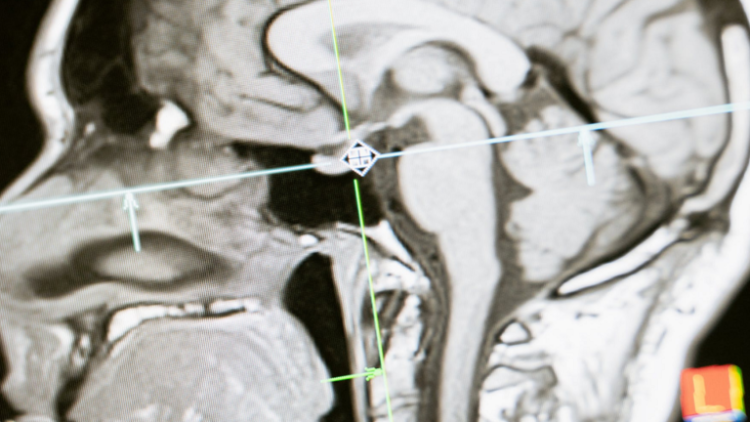

وشملت دراسة غابرييل 1601 بالغا بمتوسط عمر 76 عاما من المجموعة نفسها من المشاركين، لكنهم خضعوا أيضا لفحص التصوير بالرنين المغناطيسي لأدمغتهم في عام 2013.

وباستخدام فحوصات التصوير بالرنين المغناطيسي للدماغ، نظر الباحثون في العديد من علامات الدماغ الهيكلية، بما في ذلك حجم المادة الرمادية العميقة في دماغ كل مشارك.

وتُعرف المادة الرمادية بأنها النسيج الأكثر قتامة في الدماغ والحبل الشوكي، وهي تشارك في التحكم في العضلات والرؤية والسمع واتخاذ القرار ووظائف الدماغ الأخرى.

ووفقا لمعدي الدراسة، كلما زاد حجم المادة الرمادية في دماغ الشخص، كانت المهارات المعرفية لديه أفضل.

وفي هذه الدراسة، وجد الباحثون أنه عند مقارنتهم بالمشاركين الذين قالوا إنهم نادرا ما يشاهدون التلفاز، فإن أولئك الذين يشاهدون كثيرا لديهم كميات أقل من المادة الرمادية.

وهذا يشير إلى ضمور أو تدهور أكبر في الدماغ، وفقا لغابرييل.

وبالنظر إلى تقديرات التأثير، ارتبط متوسط وقت مشاهدة التلفاز لمدة ساعة أكثر، مع انخفاض بنسبة 0.5% تقريبا في حجم المادة الرمادية.